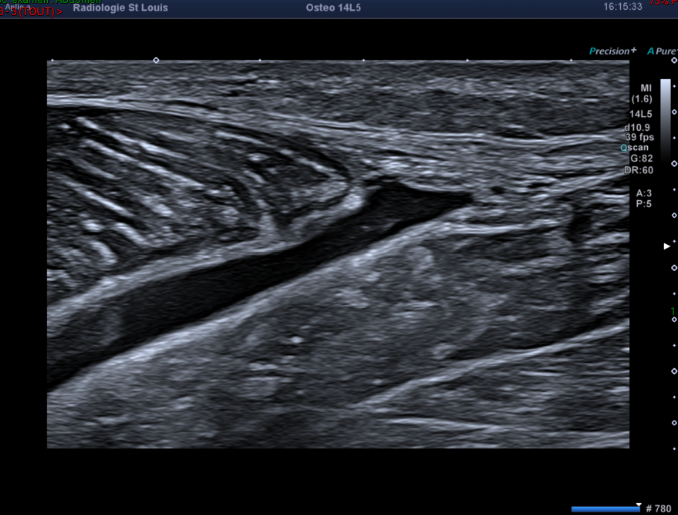

Cependant le regard de l’échographiste s’arrête sur cette image.

Que vous évoque cette collection liquidienne située entre les muscles gastrocnémien médial et soléaire ?

Il s'agit d'un hématome lié à la désinsertion myoaponévrotique au niveau de la jonction  des muscles gastrocnémien médial et soléaire, compatible avec un tennis leg.

La douleur que cette lésion musculaire provoque au mollet peut mimer une thrombose veineuse des membres inférieurs en raison de sa localisation.